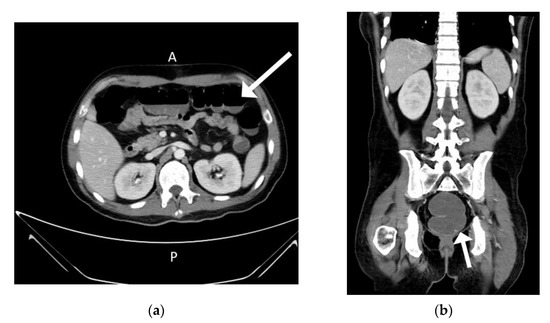

Background and Objectives: Thymomas are associated with a high frequency of paraneoplastic manifestations. Paraneoplastic syndrome (PNS) with thymoma presents a challenge to clinicians because of the need to decipher the association between the presenting symptoms and the underlying tumor. The condition most [...] Read more.

Background and Objectives: Thymomas are associated with a high frequency of paraneoplastic manifestations. Paraneoplastic syndrome (PNS) with thymoma presents a challenge to clinicians because of the need to decipher the association between the presenting symptoms and the underlying tumor. The condition most commonly noted in patients with PNS with thymoma is myasthenia gravis. Other common autoimmune diseases that may present as PNS include systemic lupus erythematosus, pure red cell aplasia, and Good syndrome. Seventy-six percent of patients with PNS-associated thymoma experience resolution of PNS after curing thymoma. Materials and Methods: A 37-year-old man with a two-month fever accompanied by polyarthritis accidently found thymoma after contrast computed tomography scans of his chest. He accepted Video assisted thoracoscopic surgery with resection of thymoma. Results: Fever and polyarthritis resolved after operation but recurred in five days due to cytomegalovirus viremia, which might be predisposed by previous antibiotics treatment before the diagnosis of thymoma. Conclusion: Patients with a thymoma also have a high frequency of PNS, and the most frequent condition found in patients with PNS-associated thymoma is myasthenia gravis. Fever with polyarthritis has been rarely reported as a symptom of PNS-associated thymoma. Here we reported an unusual case of PNS mimicking reactive arthritis with thymoma, as diagnosed based on the patient’s clinical progression, imaging examination, and laboratory tests. The patient died of his comorbidities, and his death may have been related to long-term antibiotic use and consequent intestinal dysbiosis. This challenging case may help to inform clinicians of the need for detailed work-up of fever with unknown origin in the presence of chronic polyarthritis to prevent the overdiagnosis of inflammatory arthritis or rheumatic disease and avoid further comorbidities. Detailed work-up should include the patient’s history of infections, inflammation, and malignant or nonmalignant tumors. Full article

Show Figures

Figure 1